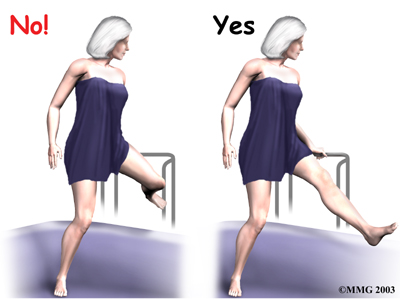

The main positions and movements to avoid after a posterior approach include crossing your legs, turning your hip and leg inward, or bending the hip more than 90 degrees.

- Don't bend the hip past ninety degrees. This means do not lean too far forward when sitting up in bed.

Also, raising your knee up in bed can cause the hip angle to go past ninety degrees.

To avoid bending past ninety degrees when sitting in a chair, lean back slightly.